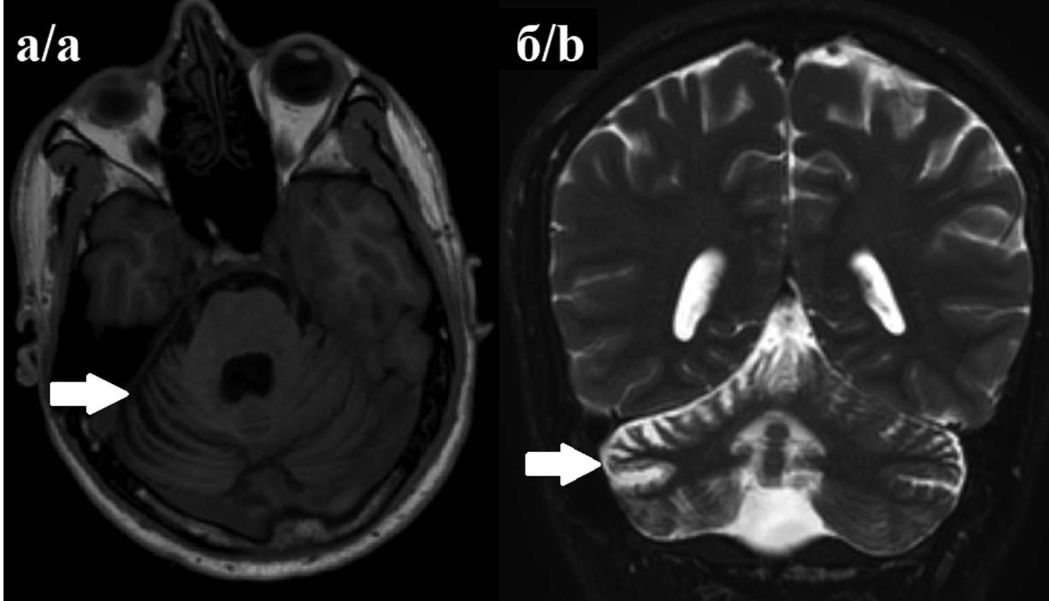

Магнитно-резонансная томография головного мозга: картина обычно остаётся нормальной на ранних стадиях, однако в ряду случаев может определяться атрофия мозжечка[5].